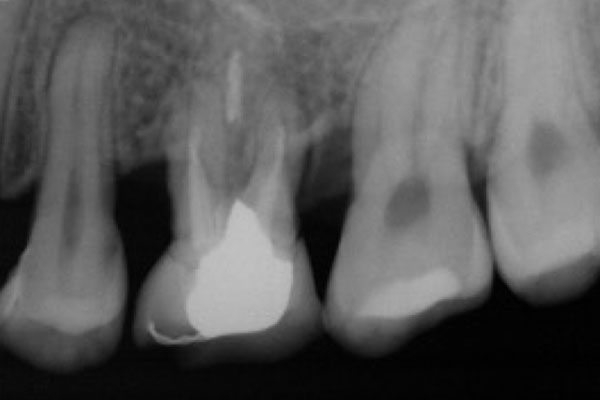

歯周病は、あごの骨を溶かす病気です。病状は歯肉の中で進行します。骨の様子を確認するため、当院では「CT」を使って検査します。

CTはレントゲンと同じくX線を用いた検査装置です。360度回転して撮影するので、あらゆる方向からの透過映像を立体的に確認でき、2次元のレントゲンより詳しく病状を把握できます。

歯周病が進行すると、歯を支えている骨が溶けて、歯がグラグラしてきます。ここまで症状が進むと「抜歯」となることが多いのですが、当院では「歯周組織再生療法」という治療法で、あごの骨の再生を目指します。骨が再生すれば、抜歯の必要はなくなります。

歯肉を切開し、あごの骨が失われた部分に「エムドゲイン」や「リグロス」という薬品を塗ることで、骨の再生を促します。個人差はありますが、数ヶ月〜1年程度で骨が再生します。